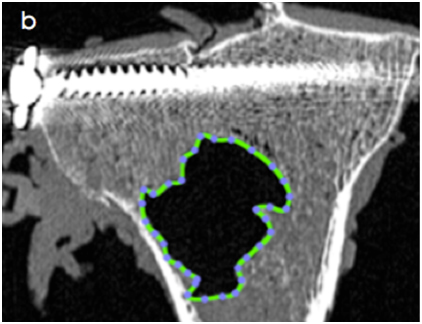

Evaluation de l’influence des implants inter épineux sur la cinématique du rachis (doctorat du Dr Fréderic Khiami)

Évaluation de l’influence des implants inter épineux sur la cinématique du rachis (doctorat du Dr Fréderic Khiami)